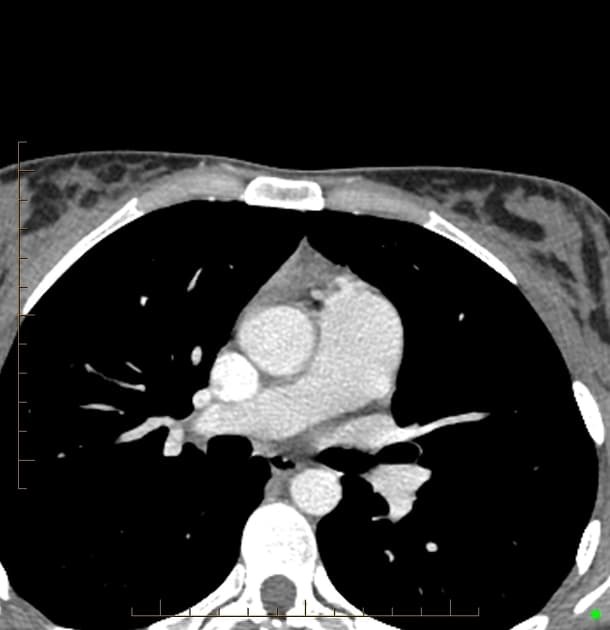

MRI gan

- Tổn thương lớn nhất nằm ở thuỳ trái gan, phân đoạn 3, có tín hiệu đồng tín hiệu (isointense) so với nhu mô gan trên hình ảnh cộng hưởng từ (MRI) trọng T1 và không giảm tín hiệu trên hình ảnh out-of-phase, điều này không gợi ý có sự hiện diện của mỡ.

- Trên hình ảnh trọng T2, tổn thương có tín hiệu đồng tín hiệu đến hơi tăng tín hiệu so với gan, với vùng trung tâm tăng tín hiệu, phù hợp với sẹo trung tâm.

- Tổn thương cho thấy tăng quang động mạch, trong đó vùng sẹo trung tâm không tăng quang, nhưng đến thì muộn thì sẹo trung tâm xuất hiện tăng quang chậm.